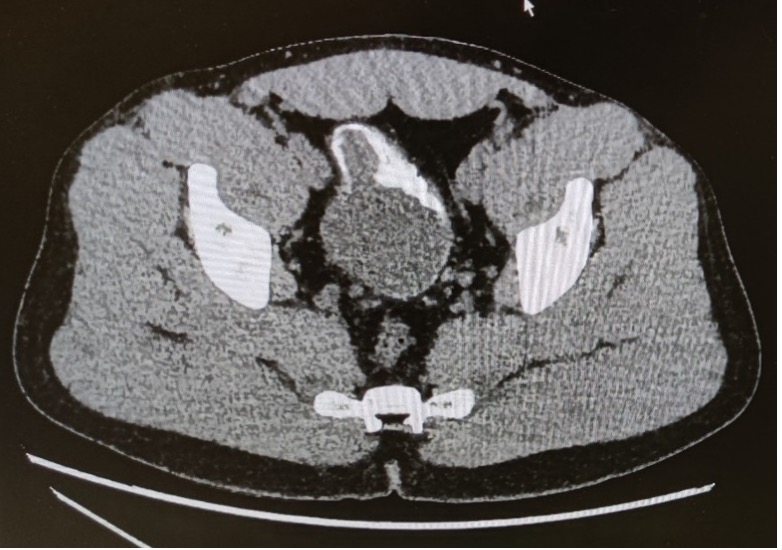

Une patiente de 34 ans, originaire d’Afrique équatoriale, en Suisse depuis 3 mois, est admise pour une douleur abdominale de la fosse iliaque gauche évoluant depuis 48h, sans défense au status. Le laboratoire met en évidence un syndrome inflammatoire. Au vu de la suspicion clinique d’une diverticulite non compliquée, un CT-scanner abdominal est réalisé.

Tu regardes les images immédiatement avec la chirurgienne, qui te confirme la présence d’un diverticule enflammé correspondant à une diverticulite Hinchey Ia. Dans l’attente des suites à donner à ce diagnostic de diverticulite, tu vois également cette image au niveau de la vessie :